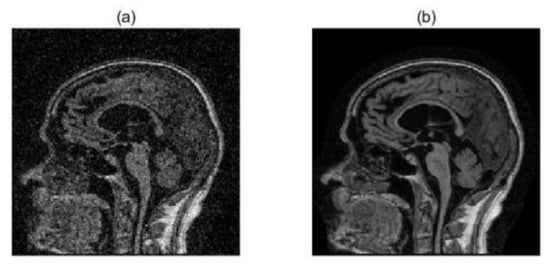

2.2. Image Preprocessing

2.3. Image Registration